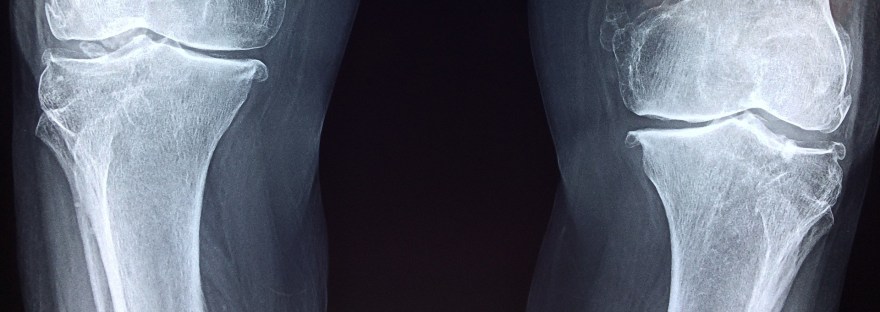

Delayed knee replacement surgery? Don’t panic – evidence suggests that it’s a blessing in disguise…

‘Prehab’ is becoming an increasingly popular approach for preparing patients for their post-operative rehabilitation stages. Knee replacement surgery is no exception!

A family member of mine is preparing for a postponed knee replacement surgery in the new year, so took a look into the research. I was pleased to find that research evidence from a number of studies has been shown to improve measures of strength and function before and after total knee replacement surgery. Here are some key points from just one study by Dr Robert Topp and his colleagues that was published in Physical Medicine and Rehabilitation in 2009: